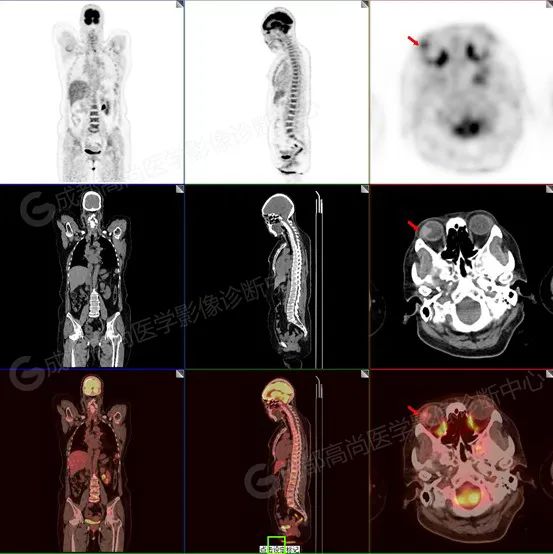

中年女性,53 岁,右眼流泪 3+月,发现右眼肿块 5 天。

2022.08.17 全身 PET/CT 融合显像

图 1-3 检查所见:紧贴右侧眼球外侧壁类三角形高密度结节突入玻璃体内(大小约 1.0 cm×1.1 cm×1.2 cm),邻近外侧和后侧眼环轻度增厚,FDG 代谢轻度增高,提示多为恶性肿瘤性病变,请结合病理。

术后病理:电话随访患方口述术后病理结果为黑色素瘤。